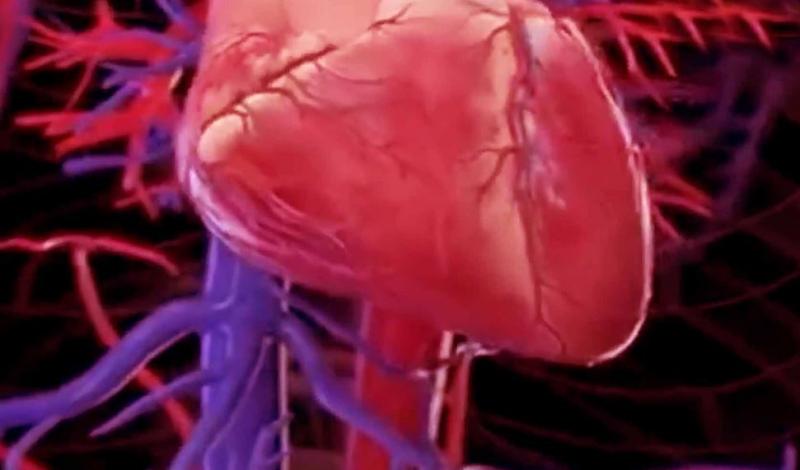

एमसी4आर जीन दिल को स्वस्थ रखने में मददगार

कैंब्रिज । एमसी4आर नामक एक जीन, जो आमतौर पर वजन बढ़ाने के लिए जिम्मेदार माना जाता है, वास्तव में हृदय को स्वस्थ रखने में भी मदद कर सकता है। यूनिवर्सिटी ऑफ कैंब्रिज की एक नई रिसर्च ने पारंपरिक सोच को चुनौती दी है। यह खोज मोटापे और दिल की बीमारियों के बीच संबंध को लेकर वैज्ञानिकों को एक नया नजरिया देती है। शोध के अनुसार, जिन लोगों में एमसी4आर जीन का एक दुर्लभ संस्करण (रेयर वेरिएंट) पाया गया, उनमें खराब कोलेस्ट्रॉल यानी एलडीएल (एडीएल) का स्तर अन्य लोगों की तुलना में काफी कम था। साथ ही, इनमें हृदय रोगों का खतरा भी अपेक्षाकृत कम देखा गया। वैज्ञानिकों का कहना है कि यह जीन लगभग एक प्रतिशत मोटे वयस्कों और करीब पांच प्रतिशत मोटे बच्चों में मौजूद होता है। ब्रिटेन में किए गए एक सर्वे के अनुसार, हर 300 में से एक व्यक्ति में इस जीन में म्यूटेशन पाया गया है।

एमसी4आर जीन मस्तिष्क में एक विशेष प्रोटीन तैयार करता है, जो भूख और ऊर्जा के स्तर को नियंत्रित करता है। सामान्य स्थिति में यह जीन व्यक्ति को जरूरत के मुताबिक भूख लगने और संतुलित भोजन करने में मदद करता है। लेकिन जब इस जीन में गड़बड़ी होती है, तो व्यक्ति अत्यधिक भूख महसूस करता है, जिससे उसका वजन तेजी से बढ़ने लगता है। यही कारण है कि इस जीन को लंबे समय से मोटापे से जोड़ा जाता रहा है। हालांकि, अब रिसर्च से यह सामने आया है कि इस जीन का दुर्लभ संस्करण शरीर में फैट मेटाबॉलिज्म को इस तरह प्रभावित करता है कि खराब कोलेस्ट्रॉल और ट्राइग्लिसराइड्स का स्तर कम हो जाता है। नतीजतन, हृदय रोग का खतरा घटता है। इस शोध में वैज्ञानिकों ने 7,719 बच्चों और 124 वयस्कों के जीन का विश्लेषण किया, जिनमें मोटापा एमसी4आर जीन के कारण था। इसके बाद उनके डेटा की तुलना यूके बायो बैंक के 3.36 लाख प्रतिभागियों से की गई।

नतीजे चौंकाने वाले थे एमसी4आर जीन वाले व्यक्तियों का ब्लड प्रेशर, कोलेस्ट्रॉल लेवल और समग्र हृदय स्वास्थ्य उन लोगों से बेहतर पाया गया, जिनमें यह जीन मौजूद नहीं था। शोधकर्ताओं का कहना है कि एमसी4आर जीन मस्तिष्क और शरीर के बीच फैट मेटाबॉलिज्म का संतुलन बनाए रखता है। यह जीन दिमाग को यह संकेत देता है कि शरीर में कितनी ऊर्जा और वसा स्टोर हो रही है। वैज्ञानिकों का मानना है कि इस जीन की कार्यप्रणाली को गहराई से समझने से न केवल मोटापे बल्कि हृदय रोग और उच्च कोलेस्ट्रॉल जैसी स्थितियों के इलाज के लिए नई दवाओं के विकास का रास्ता खुल सकता है।